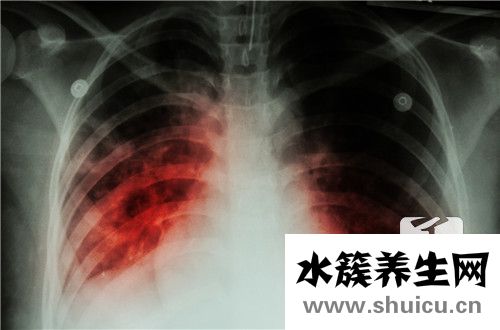

肺健康对人体非常重要,因为肺是呼吸循环的中心,人必须通过肺才能实现血液输送氧气的功能。尽管肺在体内占据了很大的体积,但它们很容易受到疾病的影响,并给人们带来很多痛苦。例如,肺部炎症是一种常见...